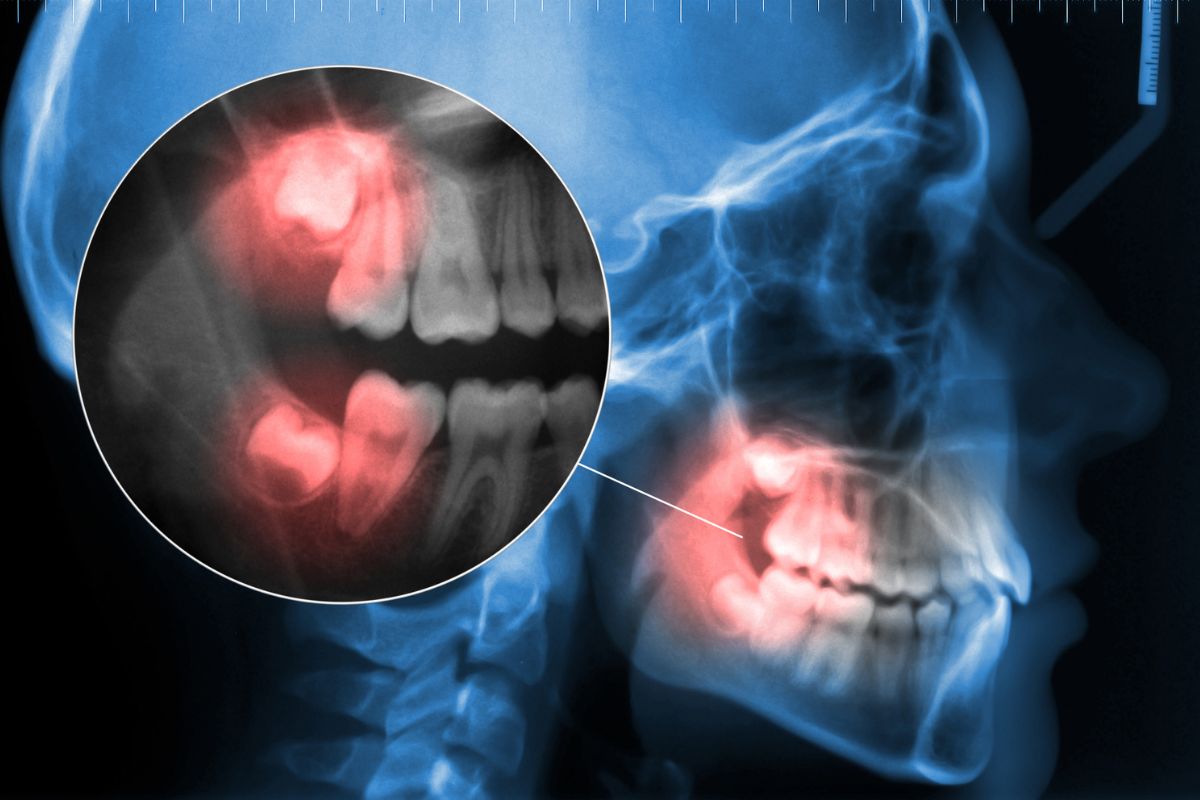

Jei išdygę protiniai dantys neišsiskiria iš bendros dantų eilių ir nesukelia diskomforto, gali nebūti reikalo jų pašalinti. Tačiau jei jie dygsta netaisyklingai arba sukelia skausmą, patartina apsvarstyti jų šalinimą.

Pagrindinis signalas, kad protiniai dantys kelia problemų, yra skausmas žandikaulyje ar burnos gilumoje. Kiti simptomai gali būti:

- dantų cistos ar infekcijos.

Pasak odontologo Nathano Yanovicho, dalinai išdygę protiniai dantys gali kelti ypatingą riziką, nes juos sunku tinkamai išvalyti, todėl didėja karieso ir dantenų ligų tikimybė.